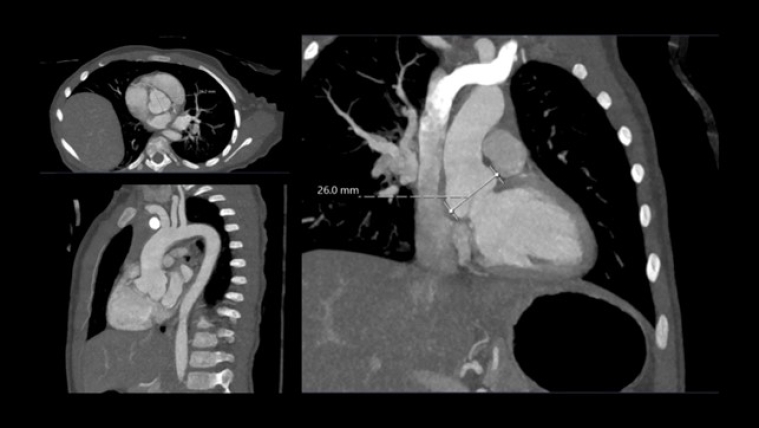

A month later she underwent cross sectional imaging. Her CT angiogram head to pelvis showed the aortic root was dilated and the thoracic aorta was elongated at the ascending and arch level, and tortuous with rightwards convexity in the descending portion. Z score Kaiser : sinus 24 x 23 mm (Z score + 4.1), ST junction 18 x 18 mm (Z score + 3.2), ascending aorta 18 x 16 mm (Z score + 3.1), transvers arch 15 x 14 mm (Z score +4.6), isthmus 9 x 9 mm (Z score + 0.5), diaphragmatic aorta 9 x 8 mm (Z score + 0.6). The brachio-cephalic arteries were dilated and tortuous.

She repeated a CT angiogram three years later that showed findings in keeping with her previous one. Z score kaiser : Sinus 26 mm (Z score + 4.7), ST junction 18 x20 mm (Z score + 2.5), ascending aorta 19 x 19 mm (Z score + 2.4), transvers arch 11 x 13 mm (Z score -0.1), isthmus 12.5 x 12.5 mm (Z score + 0.9), diaphragmatic aorta 11 x 11 mm (Z score + 1.1). Figure 4, table 1.